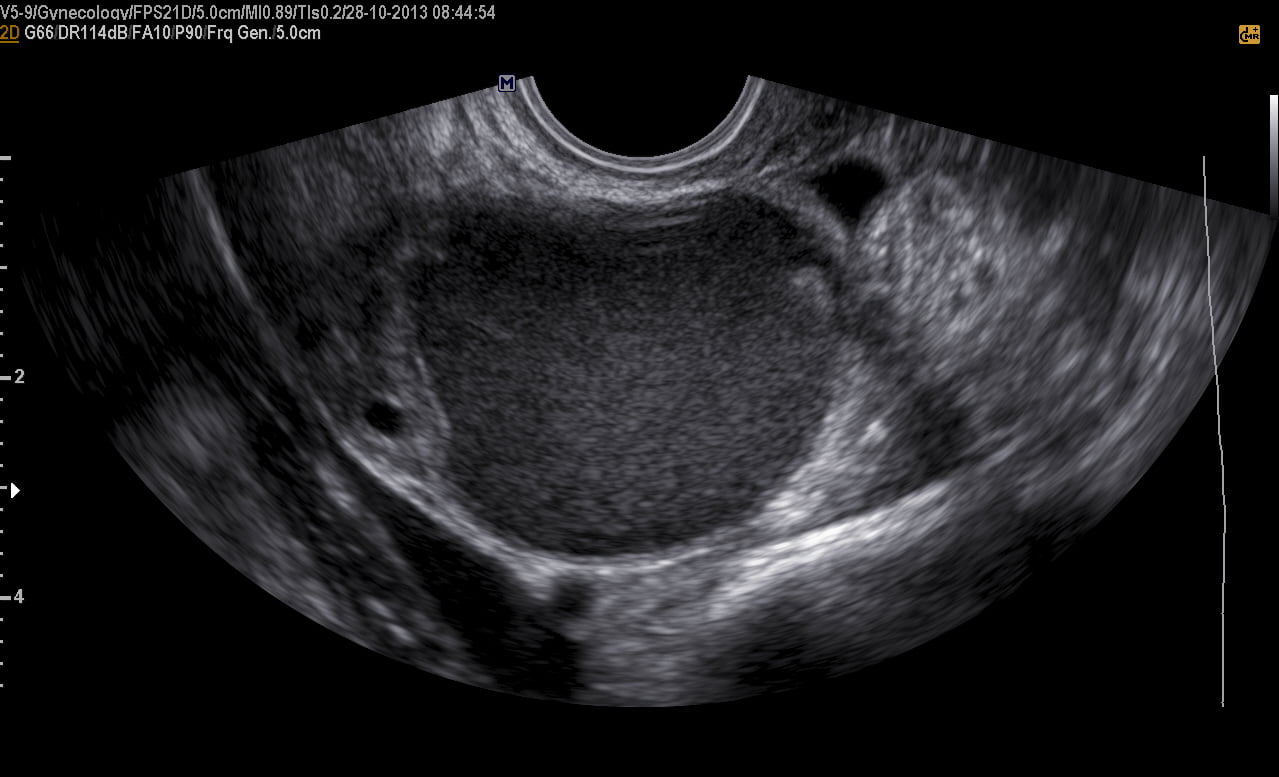

Ultrassom transvaginal com preparo intestinal demonstrando um endometrioma no ovário direito.